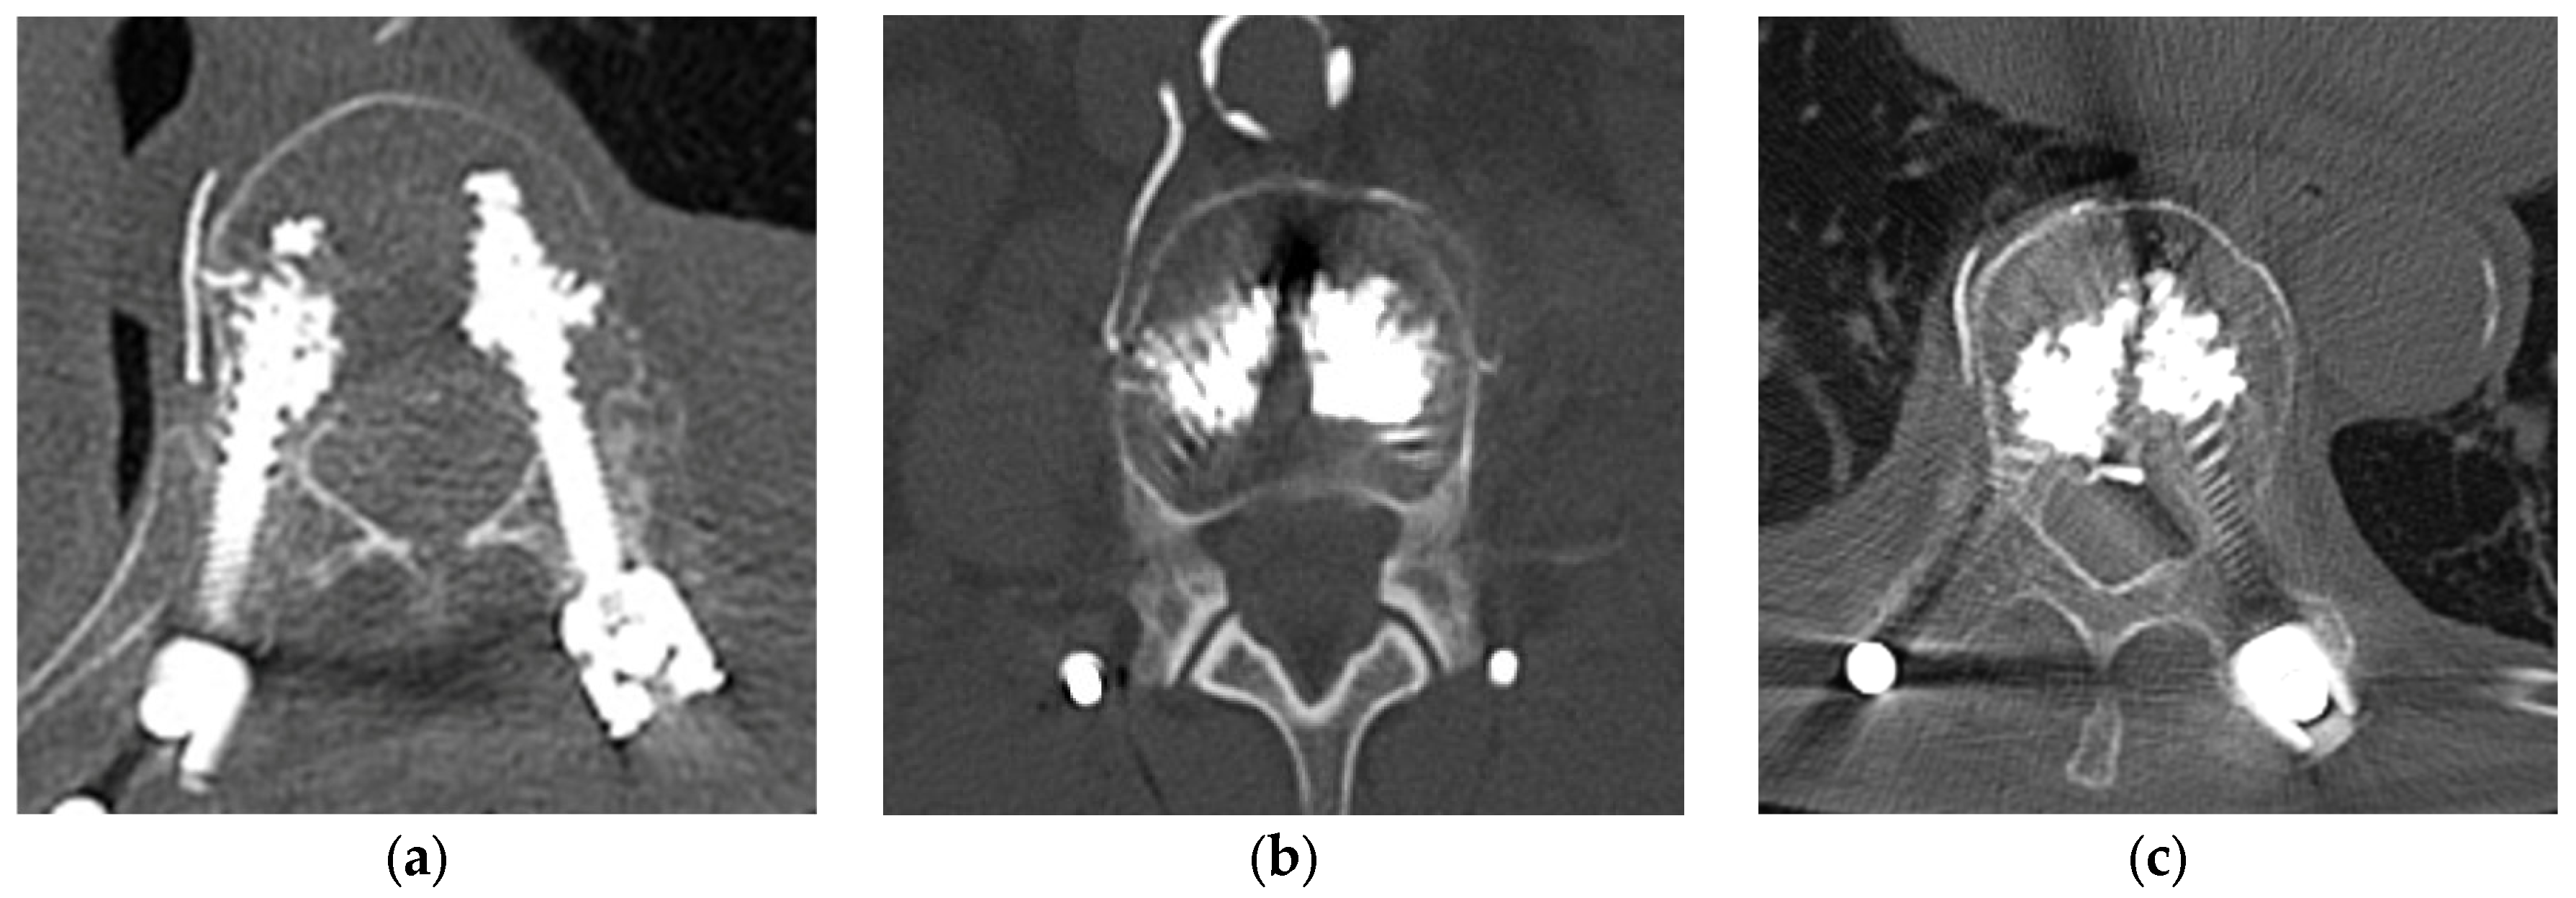

2.4. CT Evaluation and Definition of Cement Leakage

3.2. Frequency and Distribution of Cement Leakage